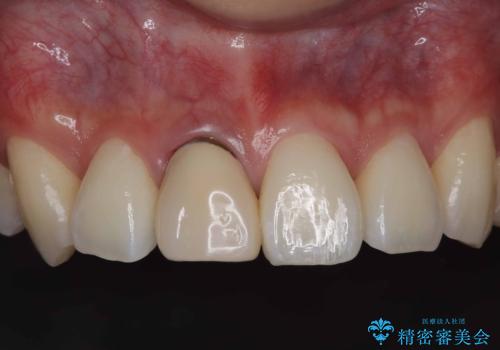

根管の充填物も不十分だったため根管治療からやり直しオールセラミッククラウンで治療を行いました。

根管の中が空洞のままで被せ物と歯のきわも合っておらず適合が悪い状態でした。根尖部付近にはパーフォレーションリペア修復の痕がありました。バイオシーシーラーを使用しシングルポイント法で充填しました。空洞があると細菌が増える環境になってしまうので、根管治療からやり直し、緊密に充填しました。被せ物の見た目も大変満足していただけました。